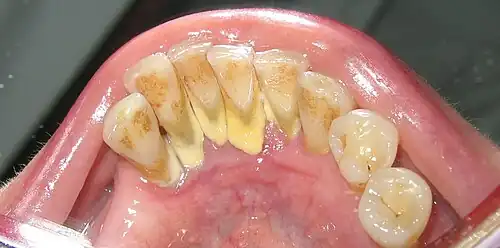

Taphonomic alterations seldom affect the teeth in the archaeological record because teeth have a high inorganic content, hence, they provide permanent records of a range of diseases. Periodontal disease, carious lesions, periapical cavities, dental calculus, intense dental wear, and ante-mortem tooth loss (AMTL) are dental conditions that are systematically recorded and studied in archaeological skeletal assemblages.[27][28] Dental diseases are especially relevant because they can provide indirect evidence of a person’s type of diet during life.[29] Furthermore, examination of the angle of tooth wear visible on the tooth crown may help differentiate dietary shifts between human populations (e.g. distinguishing hunter-gatherers and later agriculturalists).[30]

Greg Nelson and John Lukacs from the University of Oregon and Paul Yule from the Ruprecht-Karls Universität-Heidelberg in Germany analyzed AMTL, dental caries, and dental attrition in thirty-seven individuals dating to the late Iron Age in the Sultanate of Oman (100 c. BCE – 300 CE). The dental caries frequency was 35.5% and it seems that the caries onset in permanent molars began soon after eruption. AMTL occurred in 100% of preserved mandibles with frequent complete alveolar remodeling. The authors attribute the patterns observed in diets high in fermentable carbohydrates, known to be highly cariogenic (e.g. dates).[31]